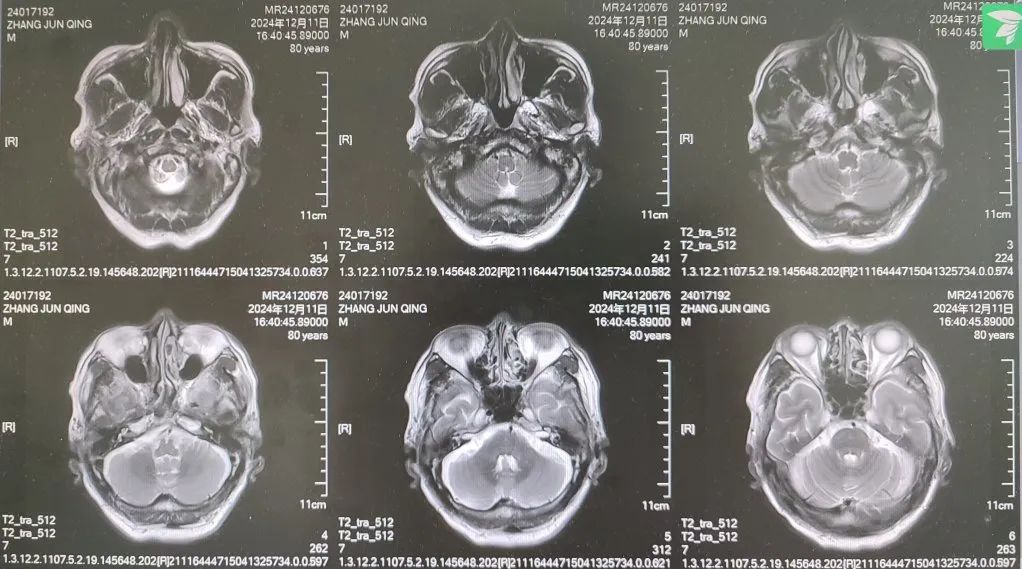

內(nèi)容提要 很多人都想擁有纖細(xì)、健美的雙腿,嘗試多種健身方法,效果卻始終不理想。然而社會(huì)上大約有萬分之四的人,他們不用減肥,雙腿就會(huì)慢慢“瘦”下來,如倒置的香檳酒瓶,醫(yī)學(xué)中稱之為“鶴腿”。不過這并非自愿,而是源于一種名為“腓骨肌萎縮癥”的罕見疾病。近日,市二院神經(jīng)內(nèi)二科趙智江主任團(tuán)隊(duì)就幫助一位受腓骨肌萎縮癥困擾4年之久的患者明確了病因。 #01 “鶴腿”多年不明病因 竟是罕見病作祟 患者80歲,四年前無明顯誘因出現(xiàn)步態(tài)異常,行走困難,起初以為是勞累所致,并未過多在意。然而,近一年來癥狀逐漸加重,雙下肢膝關(guān)節(jié)以下麻木、發(fā)涼,行走時(shí)右下肢有甩腳動(dòng)作,呈跨閾步態(tài),右足趾背屈不能,同時(shí)存在站立不穩(wěn)、不能蹲下等癥狀,嚴(yán)重影響日常行走。這一年間,他輾轉(zhuǎn)市內(nèi)多家醫(yī)院,經(jīng)歷了無數(shù)次的檢查和咨詢,卻始終未能得到確切診斷。 近日,患者經(jīng)多方打聽,來到了以診治神經(jīng)疑難病為特色的市二院神經(jīng)內(nèi)二科。入院后,趙智江主任為患者進(jìn)行了細(xì)致入微的查體,發(fā)現(xiàn)患者雙側(cè)大腿下三分之一處及小腿肌肉萎縮。進(jìn)一步完善頭顱、頸椎及胸椎核磁的檢查,由于患者存在跨閾步態(tài),結(jié)合檢查結(jié)果,初步考慮為腓總神經(jīng)麻痹。 頭顱、頸椎核磁回報(bào)后,基本上排除了神經(jīng)根的疾病和脊髓疾病。肌電圖結(jié)果提示四肢周圍神經(jīng)受累,右側(cè)腓總神經(jīng)損傷更重,修正診斷為周圍神經(jīng)病。然而,周圍神經(jīng)病存在多種病因,需進(jìn)一步查找病因。趙智江主任結(jié)合患者雙下肢肌肉萎縮情況,排除其它病因?qū)е碌闹車窠?jīng)病,最終明確診斷為腓骨肌萎縮癥。 頭顱核磁影像 頸椎及腰椎核磁影像 隨后,中國醫(yī)科大學(xué)附屬第一醫(yī)院神經(jīng)內(nèi)科著名專家何志義教授及遼寧名醫(yī)、市二院卒中中心主任閔連秋教授在查房時(shí)同樣肯定了腓骨肌萎縮癥的診斷。 腓骨肌萎縮癥是一組具有高度臨床和遺傳異質(zhì)性的周圍神經(jīng)單基因遺傳病,以慢性進(jìn)行性四肢遠(yuǎn)端肌無力肌萎縮、末梢型感覺障礙、腱反射減退或消失和高弓足等骨骼畸形為主要臨床特征,多為兒童和青少年期起病。該患者老年起病,極為罕見!目前,腓骨肌萎縮癥無特效治療藥物,主要以支持治療為主。今后,患者只要在康復(fù)醫(yī)師的指導(dǎo)下,根據(jù)神經(jīng)損害范圍進(jìn)行合理的康復(fù)鍛煉,就能保持較好的活動(dòng)能力,提高生活質(zhì)量。 市二院神經(jīng)內(nèi)二科趙智江主任團(tuán)隊(duì)擁有豐富的神經(jīng)系統(tǒng)疑難疾病診治能力,曾幫助大量飽受罕見病困擾多年的患者明確了診斷。隨著診療水平的持續(xù)精進(jìn),神經(jīng)內(nèi)二科將為更多患者提供精確診斷及治療,為更多的神經(jīng)疑難疾病明確診斷,為患者帶來福音。 #02 人民醫(yī)院 人民名醫(yī) 趙智江 主任醫(yī)師 副教授 ·葫蘆島市第二人民醫(yī)院神經(jīng)內(nèi)二科主任 ·中國卒中學(xué)會(huì)高級(jí)會(huì)員 ·中國老年保健醫(yī)學(xué)研究會(huì)老年腦血管病分會(huì)委員 ·北京神經(jīng)內(nèi)科學(xué)會(huì)腦小血管病學(xué)會(huì)委員 ·安徽醫(yī)藥雜志審稿專家 專業(yè)特色:以腦血管病為核心研究方向,擅長各類神經(jīng)系統(tǒng)疾病的診療,尤其在腦血管病、帕金森綜合征、頭暈、頭痛、癲癇、重癥肌無力以及中樞神經(jīng)系統(tǒng)脫髓鞘等神經(jīng)系統(tǒng)疑難、危重疾病的診療方面積累了豐富的臨床經(jīng)驗(yàn)。主持多項(xiàng)重要科研項(xiàng)目,并將最新的科研成果應(yīng)用于臨床實(shí)踐,撰寫十余篇論文著作。